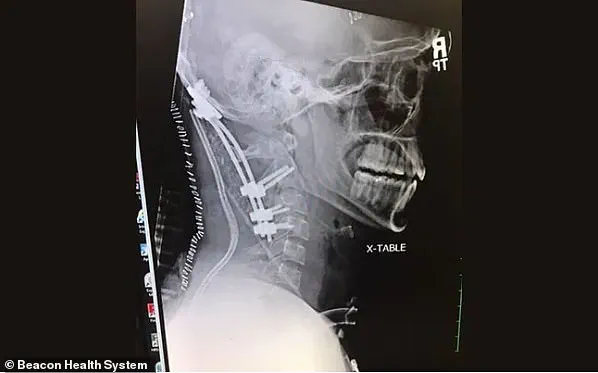

To stabilize this critical condition, doctors performed a posterior occipito-cervical fusion—a complex surgery involving rods, screws, and bone grafts—to permanently fuse Brock’s skull to his upper cervical vertebrae.

This intricate procedure not only helped prevent further damage but also ensured that any movement of the neck was restricted.

Doctors diagnosed Meister with Type 1 internal decapitation, where the skull is displaced forward on the neck.

The other two types include displacement upward (Type 2) and backward from the neck (Type 3).